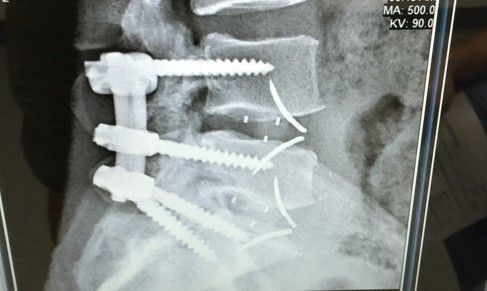

Here's my new titanium hardware. Should I compare it to the material that it replaced?

Power to the Metal! Damn, those screws look huge, though.Here's my new titanium hardware. Should I compare it to the material that it replaced?

Yeah they're pretty gnarly. I finally get to walk around without that damn uncomfortable brace now. Whew, that sh** has been rough!Power to the Metal! Damn, those screws look huge, though.